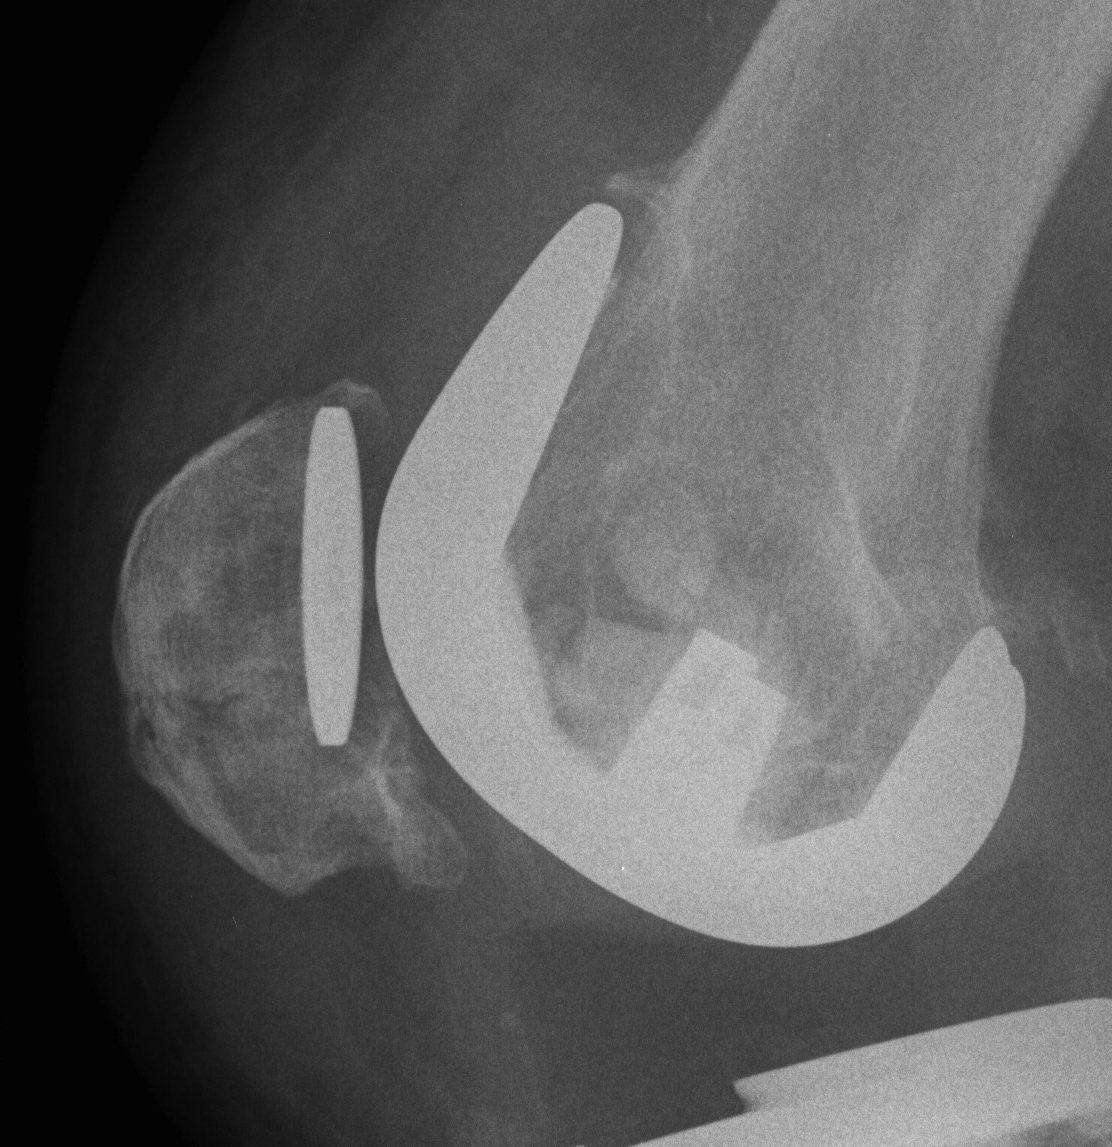

Xray

- skyline views

- lateral tilt / subluxation